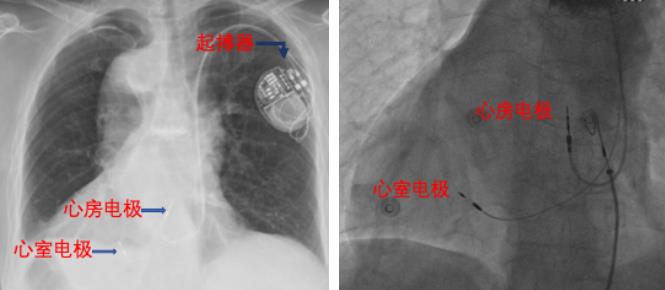

正常人心率为60-100次/分,而该患者外院动态心电图提示平均心率44次/分,最慢28次/分,同时有短暂全心停搏3.5s,需植入起搏器帮助患者提升心率。患者择期入导管室,因为其心脏位于胸腔的右侧,选择从右侧腋静脉入路,送入导丝后发现导丝无法到达右心室,前路“荆棘丛生”,真的是“山穷水尽疑无路”吗?为明确心脏结构和血管行走路线,术者沿导管向心腔内不同位置及左手静脉留置针注射造影剂,此时“柳暗花明又一村”,发现患者不仅为镜像右位心,且合并静脉血管畸形,存在“永存右上腔”(即永存左上腔的镜面反应,永存左上腔为静脉畸形,由胎儿期的左前主静脉与左Cuiver管不闭合而形成,多引流入冠状静脉窦),同时上腔静脉位于左侧,而正常人的上腔静脉位于右侧,这类患者极其罕见,在我院起搏器植入手术史上尚属第一次,当时我院正在举办希浦系统起搏培训班,即刻引起了来自全国各地学习交流的20多位专家的特别关注。

为患者的长期预后考虑,此时心内二区的方咸宏主任携手温州医科大学黄伟剑教授决定首次尝试为复杂先心病患者进行希浦系统生理性起搏,当即改从左侧腋静脉入路,并对送入心室电极的HisC315鞘进行塑形,旋入心室电极至左室间隔内膜面并记录到左束支电位,证实起搏电极已到达左束支区域,手术顺利完成,术后患者恢复良好,第四天出院。